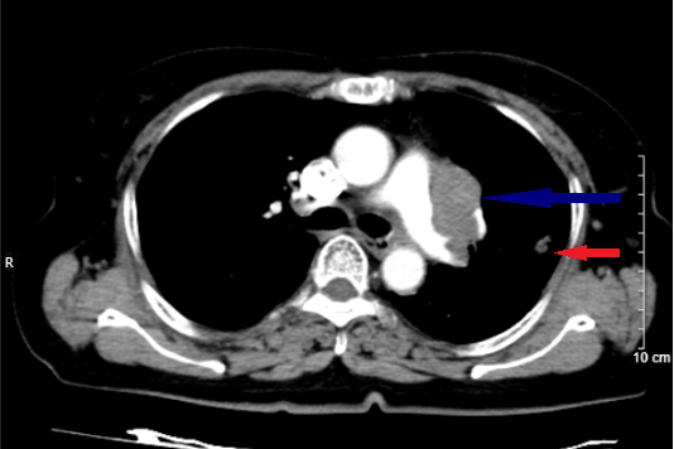

Bệnh viện Bãi Cháy đã phẫu thuật nội soi thành công khối u trung thất sát cột sống

cho bệnh nhân 38 tuổi, giúp bệnh nhân thoát khỏi nguy hiểm.